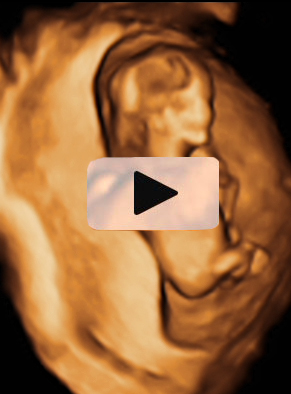

Ecografía Embarazo 4D Semana 12 - PRUEBAS DIAGNÓSTICAS